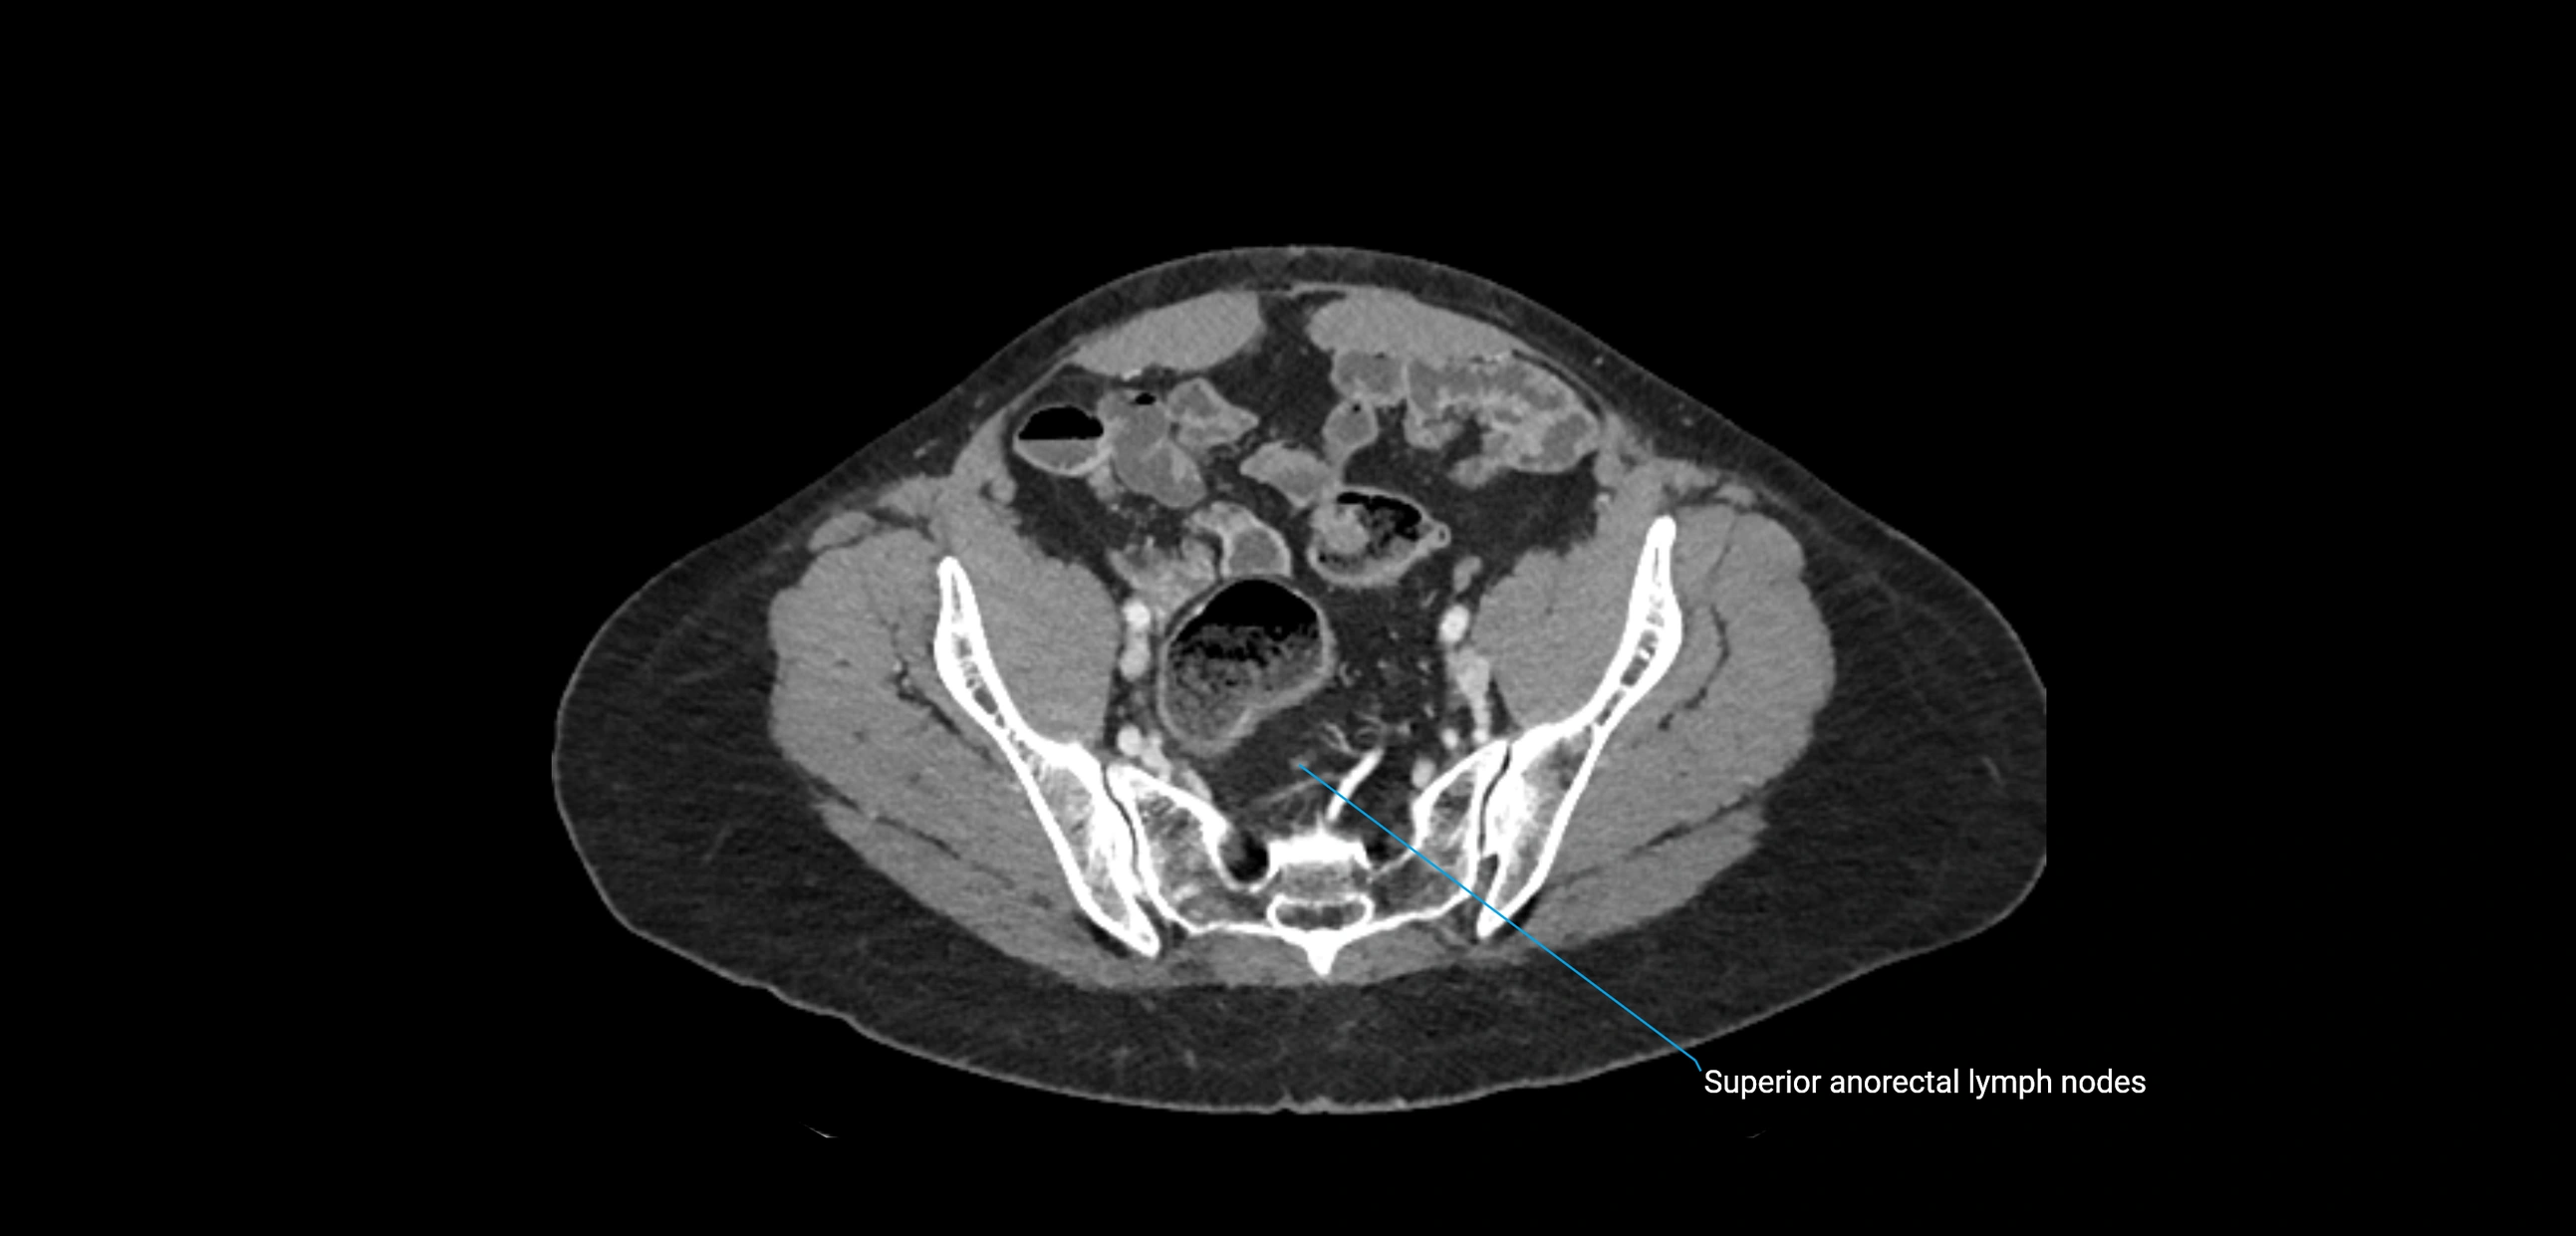

CT Appearance

CT Post-Contrast:

• Normal nodes enhance homogeneously

• Malignant nodes may show heterogeneous enhancement, central necrosis, or conglomerate formation

• Size >1 cm short axis is suspicious, though morphology and distribution are equally important